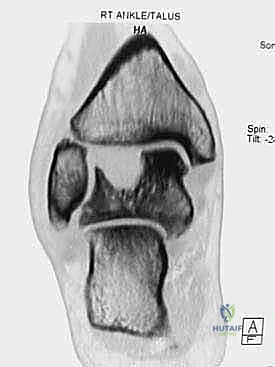

تبدأ رحلة العلاج مع الأستاذ الدكتور محمد هطيف بتقييم شامل. يتم إجراء فحوصات دموية كاملة، وتخطيط للقلب، والأهم من ذلك: التصوير الطبي المتقدم.

يعتمد الدكتور هطيف على الأشعة السينية (X-rays) والأشعة المقطعية (CT Scans) ثلاثية الأبعاد لبناء خريطة دقيقة للتشوهات العظمية وتحديد حجم ومسار المسمار النخاعي المناسب لكل مريض بدقة متناهية. يتم مناقشة كل هذه التفاصيل بشفافية تامة مع المريض.